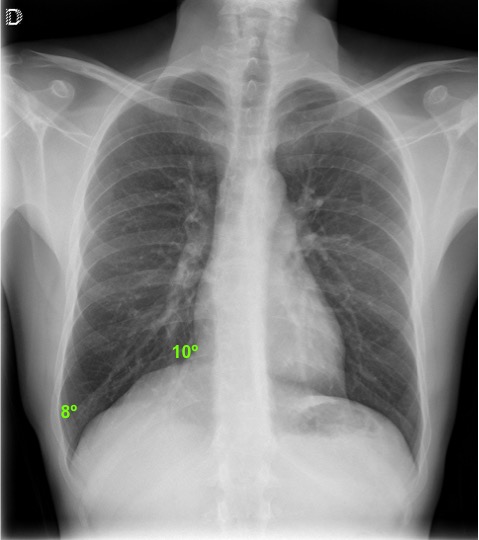

CASO: sospecha de neumonía.

Hallazgos:

- En un principio podríamos decir que existe un aumento de densidad retrocardiaco que podría ser compatible con condensación neumónica a dicho nivel, sin embargo estamos ante una placa poco inspirada, lo cual puede llevarnos a cometer errores diagnósticos.

- Se recomendó volver a realizar la radiografía, observar a continuación:

Ya no se observa el aumento de densidad retrocardiaco, la placa es normal.

INSPIRACIÓN: Una placa bien inspirada es aquella en la que se observar 6-7 arcos costales anteriores o 10-11 arcos costales posteriores. Lo contrario puede producir imágenes falsas de condensaciones o de seudocardiomegalia.